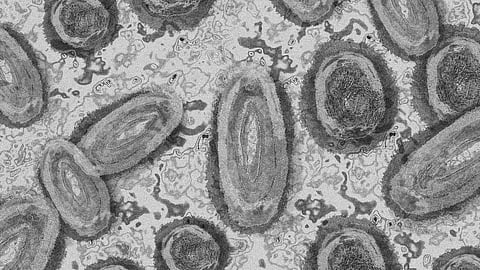

Mpox attacks the body like a vesicular disease, such as smallpox, which causes skin lesions. As part of the original study, Dr. Martinot evaluated whether a first infection or second infection leads to the characteristic “pox” skin lesions.

“Monkeys that had one infection did develop skin lesions,” she says. “And we noticed that the animals had several other lesions that have not been previously described in people, so that’s one of the things that I’m working to try to understand.” Monkeys that had a second infection did not develop the classic pox skin lesions, and this corresponded to their strong immune responses against the virus.

During the course of the study, researchers detected the mpox virus in the skin, cervix, uterus, and periovarian endometriosis lesions in a female rhesus macaque with severe endometriosis (when endometrial tissue is found outside the uterus). This finding indicated that women may be at higher risk of mpox if pregnant or suffering from endometriosis. Dr. Martinot felt this warranted further study and pulled in a team at Cummings School.

“The fact that we found mpox lesions in the female reproductive tract was an interesting case,” says Hall. “Mpox is mostly seen in men, but it’s just as infectious in women. We thought this was a strong enough story to get the information out there, to help both animal researchers and doctors have an understanding of the pathogenesis.”

Li explains the significance of the team’s research, “Description of mpox lesions in the reproductive tract of women is limited, and assessing the lesions in human patients is difficult and invasive. The rhesus macaque is a useful model since it has a similar reproductive anatomy to humans. This case report will help us understand mpox lesions in the reproductive tract and raise awareness of potential similar lesions in human patients.”

“No research has been published for human women showing monkey pox in the reproductive tract anywhere other than the outside surface of the cervix,” says Dr. Lyons. “This research brings attention to the potential for the virus to travel outside of the uterus. Endometriosis is such a prevalent condition and can spread through the abdomen. Mpox might impact tissues that endometrial lesions are attached to.”